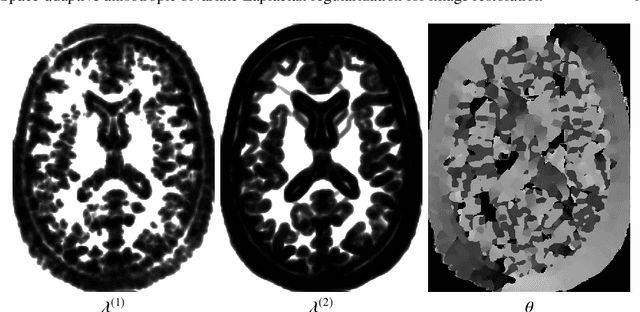

Abstract:In this paper we present a new regularization term for variational image restoration which can be regarded as a space-variant anisotropic extension of the classical isotropic Total Variation (TV) regularizer. The proposed regularizer comes from the statistical assumption that the gradients of the target image distribute locally according to space-variant bivariate Laplacian distributions. The highly flexible variational structure of the corresponding regularizer encodes several free parameters which hold the potential for faithfully modelling the local geometry in the image and describing local orientation preferences. For an automatic estimation of such parameters, we design a robust maximum likelihood approach and report results on its reliability on synthetic data and natural images. A minimization algorithm based on the Alternating Direction Method of Multipliers (ADMM) is presented for the efficient numerical solution of the proposed variational model. Some experimental results are reported which demonstrate the high-quality of restorations achievable by the proposed model, in particular with respect to classical Total Variation regularization.